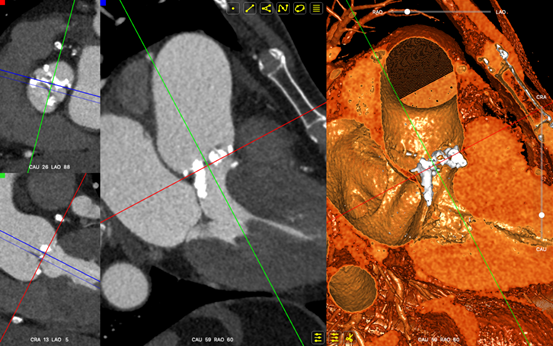

主动脉根部分析:

主动脉瓣二瓣化畸形重度钙化并重度狭窄(钙化积分达1368)、升主动脉扩张;平均跨瓣压差为52mmHg;左室舒张末直径41 mm;EF 51%。

二叶瓣严重钙化